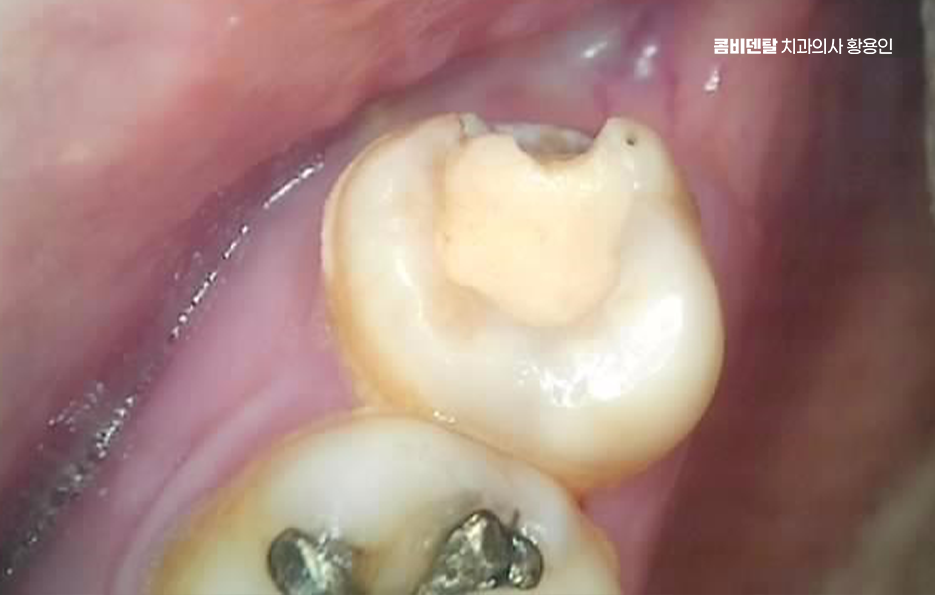

출처 아카이브 열기처음 인레이 치료를 받았을 땐, 사실 그렇게까지 큰일로 받아들이진 않았어요. 치아에 충치가 조금 생겼고, 그걸 레진으로 떼우기에는 깊이가 있고 강도도 걱정된다고 해서 인레이 치료를 권유받았어요 실제로 치료 이후엔 전혀 불편함이 없었어요. 음식을 씹을 때도, 양치를 할 때도, 입 안에 이물감이 없다 보니 마치 원래부터 그 상태였던 것처럼 느껴졌고, 인레이를 했다는 사실조차 자주 잊고 살았어요. 특히 충치 때문에 겪었던 찌릿한 통증이 완전히 사라졌고, 이제는 완전히 문제가 해결되었다는 안도감이 오히려 방심을 불러왔던 것 같아요. 그러다 시간이 조금씩 흘렀어요. 1년, 2년, 그렇게 몇 해가 지나면서도 딱히 문제는 없었어요. 워낙 바쁜 일상에 치과 검진은 늘 뒷전이었고, 양치는 하루 두 번이면 충분하다고 생각했고, 커피를 하루 세 잔 마셔도, 견과류를 매일 씹어도, 나름 치아 건강엔 자신이 있었어요. 그렇게 습관처럼, 인레이 치료 이후의 관리도 습관처럼 대충 넘기면서 살아왔는데, 언제부턴가 이상한 느낌이 시작됐어요. 처음엔 음식물이 잘 껴서 불편하다는 정도였어요. 인레이가 들어간 그 어금니 쪽에 자꾸 음식물이 끼고, 양치 후에도 뭔가 남아있는 것 같은 찝찝함이 있었는데, 그러려니 하고 치실로 해결했어요. 그런데 어느 날은 뭔가를 씹는 순간, 딱딱한 게 이 사이에서 순간적으로 미끄러지는 느낌이 들었고, 그 뒤로는 그 치아에 약간의 통증이 찾아왔어요. 처음엔 무시했어요. 치아가 민감해졌나 보다, 며칠 지나면 괜찮아지겠지 하면서 대수롭지 않게 여겼고, 진통제를 한두 번 먹으면 어느 정도 괜찮아졌기 때문에 또 방심하게 됐어요. 하지만 그 시기가 지나면서부터 상황은 급격히 나빠졌어요. 통증은 더 자주, 더 깊이 왔고, 뜨거운 국물을 마실 때나 차가운 음료를 마실 때, 유난히 그 치아 하나가 반응을 하더라고요. 특히 씹을 때 그 치아에 미세한 통증과 묘한 압력이 느껴지는데, 그게 그냥 아프다는 차원이 아니라 안에서 무언가 망가지고 있다는 감각이었어요

인레이 치료 후 신경치료 까지 가는 대표적인 케이스 중 하나는 2차 충치, 그러니까 인레이와 치아 사이에 다시 충치가 생기는 경우로서 인레이는 금이나 세라믹 같은 재료로 제작되는데 아무리 정밀하게 맞췄다 해도 그 접합부는 시간이 지나면서 아주 미세한 틈이 생길 수 있어요.

거기에 음식물이나 세균이 침투하게 되면 눈에 보이지 않는 사이에 충치가 다시 시작되는 것이며 특히 칫솔질만으로는 인레이 경계 부분을 완전히 관리하기 어렵고 치실이나 치간칫솔 사용이 소홀한 분들에게 이런 2차 충치가 더 자주 생길 수 있었어요

두 번째로는 보철물 자체가 파절되는 케이스로 인레이는 치아 만큼이나 강하지만 부서지지 않는 건 아닌데 특히 딱딱한 음식이나 얼음, 오징어 같은 질긴 걸 자주 씹는 습관이 있는 경우, 반복적인 교합 압력 때문에 인레이가 금이 가거나 쪼개지는 일이 생길 수 있으며 이때 보철물이 살짝 금 간 정도면 다시 본을 떠서 인레이를 교체하면 되는데 문제는 인레이가 파절되면서 그 안에 있는 치아 조직까지 손상시키는 경우로 치아는 한 번 금이 가기 시작하면 내부까지 확산되기 쉬워서, 그 틈을 따라 세균이 침입하고 결국 치수염, 즉 신경에 염증이 생기게 되는 거예요.

인레이 치료 후 신경치료 케이스 다음으로는 인레이 아래쪽 치아 균열이나 미세 파절이 이미 진행 중이었는데 발견이 늦어진 경우로 이런 경우는 환자 본인이 특별히 통증을 느끼지 않는 한 알기 어렵고, 인레이 치료 후 한동안 잘 쓰다가 갑자기 시큰거리거나 찬물에 민감해지면서 이상을 느끼게 되는데 엑스레이로도 미세 균열은 바로 확인이 어렵기 때문에 증상이 나와야 겨우 파악되며 이때는 신경까지 손상이 된 경우가 많아서 결국 신경치료를 해야 하는 상황으로 연결되는 경우도 있었어요